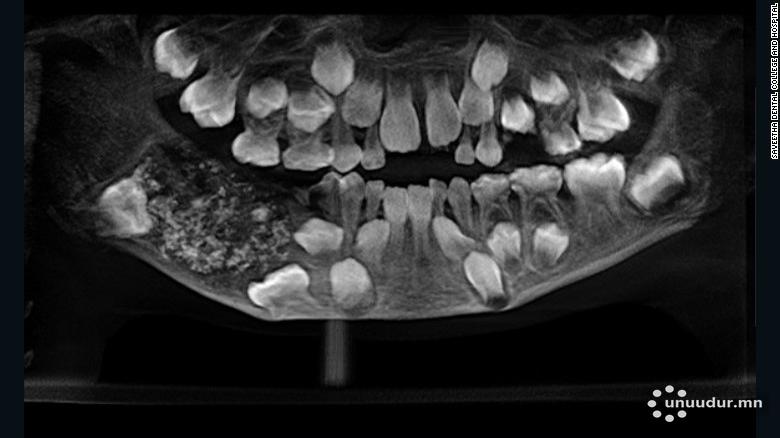

Түүний амны орчмыг рентгенд харахад доод эрүүнд хэвийн бус шүд ургасан уутанцар харагдсан байна. Эмч нар олж мэдсэн зүйлээ батлахын тулд шүд тус бүрийг нэг бүрчлэн шалгаж үзэх шаардлагатай болжээ. Хүүгийн шүдийг авах мэс заслыг өнгөрсөн сард хийсэн бөгөөд хагалгаа 4-5 цаг үргэлжилжээ.

Нийтдээ 526 шүд нь 0.1-15 миллиметр хэмжээтэй байв.